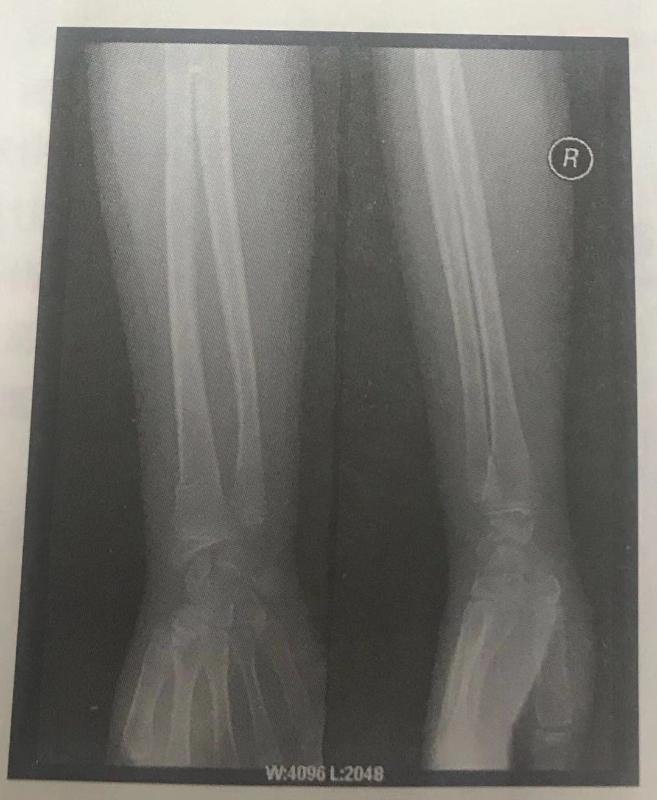

根據(jù)下面X線片判斷臨床意義。(5分)

右撓骨遠(yuǎn)端青枝骨折。